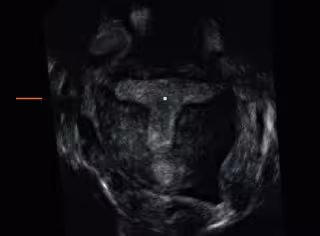

El 'útero en T' provoca abortos de repetición y mayor frecuencia de partos prematuros

Un útero en forma de T

Los denominados 'úteros en T', una anomalía que entraña una forma estrechada y tubular de la cavidad endometrial, provocan mayor aparición de dismenorrea o dolor durante la menstruación, mayor frecuencia de fallos de implantación embrionaria, abortos de repetición y una mayor frecuencia de partos prematuros.

"La ecografía 3D permite la evaluación integral del útero, de manera sencilla, rápida y detallada. Así pues, la obtención de planos coronales uterinos permite valorar la morfología de la cavidad endometrial de modo directo, siendo este factor un notable avance sobre las técnicas ecográficas convencionales basadas en 2D", ha explicado el director médico de IVI, el doctor Antonio Requena.